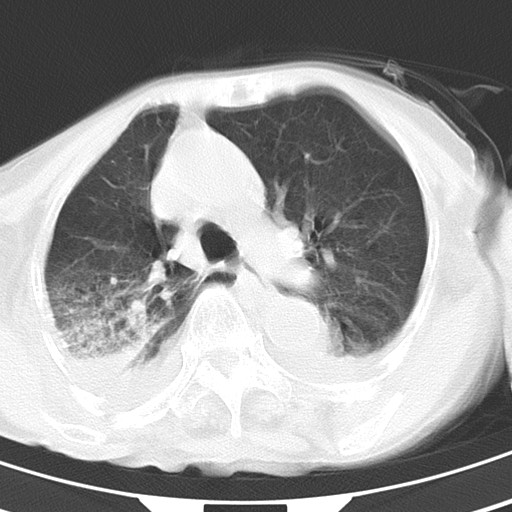

女,93岁,摔伤后检查。

右肺炎症,心功能不全伴双侧胸腔积液,右下肺膨胀不全,食管裂孔疝,冠脉钙化,心包少量积液,左侧肋骨骨折,请上传骨窗.

双肺感染合并双侧胸腔积液、胸膜增厚粘连,骨性胸廓未见明确骨折征。

创伤性湿肺,双侧胸腔积液。可能有食管裂孔疝,进一步检查。骨折有无根据自己的机器及片子再仔细看吧。

右侧锁骨\\肩胛骨骨折、右侧湿肺,心功能不全伴双侧胸腔积液,右下肺膨胀不全,左膈破裂或食管裂孔疝,冠脉钙化,心包少量积液,请上传骨窗.

右肺炎症,心功能不全伴双侧胸腔积液,右下肺膨胀不全,食管裂孔疝,冠脉钙化,心包少量积液,左侧肋骨骨折,右肩甲骨粉碎性骨折。93岁,高寿哇!

右肺炎症,心功能不全伴双侧胸腔积液,右下肺膨胀不全,食管裂孔疝,冠脉钙化,心包少量积液,左侧肋骨骨折,右肩甲骨粉碎性骨折。